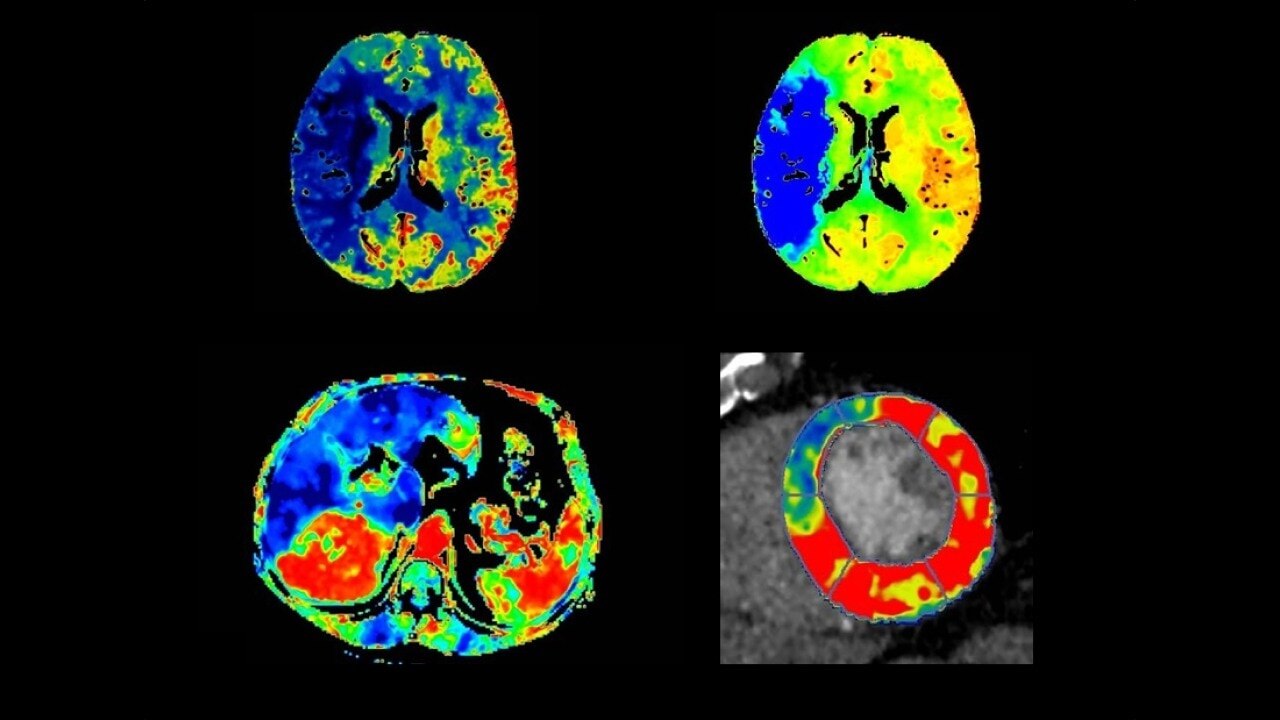

CT Body Tumor Protocol

• Automatically produces functional maps once the user selects an artery using a simple and intuitive workflow

• Leverages most of the advanced algorithm settings that are part of the Brain Stroke protocol

• Optimized protocols for pancreas, prostate, kidney, soft tissue, spleen, bone and liver perfusion

• CT Non-Rigid Registration: Fully automated protocols used for dynamic body acquisitions to register data for use in perfusion analysis